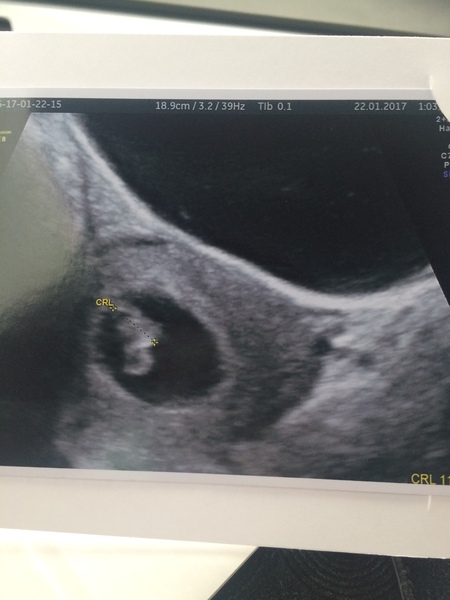

MouseLove · 21/01/2017 12:18

Back home. Took ages despite being in first at 8am this morning.

We saw baby's heartbeat ❤️ and everything looks good. Measuring a little smaller at 5ish weeks but baby is so small at this stage they said not to worry. I have a little cyst but nothing to worry about. Sack looks perfect shape and measured 10mm. Baby is 2mm. I go back in 2 weeks for another scan but they said it was more so just to tick a box, doctor was happy for me to wait for my 12 weeks scan now.

So, I emptied my bladder just as they called my name. I have seriously bad timing but I couldn't hold it any longer as I'd been sat for almost 2 hours by the time I was scanned. So I ended up having an internal scan too. That's when we saw baby and the flickering on screen. We're both so happy and relieved. Obviously hoping baby is growing well the next few weeks with me being on medication now too.

Thank you for all the well wishes and lovely words of encouragement. Means a lot!! X

ns1348 · 21/01/2017 13:40

Yay Mouse, congrats, that's great! Sod's law they took you in just after you'd peed! Really pleased for you after your worry. And yes science is amazing Mrs G, isn't it!

Our scan went well too thankfully! Baby is in right place, and we saw a heart beat too, which I thought was amazing at 5mm, but even more so for you Mouse. Think size-wise we're a day or two behind expected, but all good. DH nearly cried!

MouseLove · 21/01/2017 14:15

Awwww ns that's brilliant news!!! And fantastic size too!! I have a feeling they might go off sack size for baby at this stage so you must have a nice juicy sack. 😎🙊

Heartbeat. Wow. That little flickering. I was in tears. ❤️😘

Dixiechick1991 · 22/01/2017 14:52

Hello. WEnt for another reassurance scan today after being told last week that I was only 5-6 weeks, I'm now 7+3 with baby measuring 11.5mm and a tilted uterus.

Got to see a tiny little blob with a heartbeat & new due date of 7th September